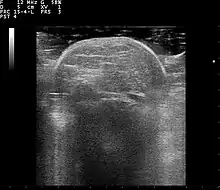

Lipoma ultrasound 110322120428 1206550

Familial multiple lipomatosis is usually diagnosed through a physical exam via palpation, medical history and imaging studies such as ultrasound, CT scan, or magnetic resonance imaging (MRI). A CT scan is an imaging method that uses x-rays to create images of cross sections of the body, while an MRI uses powerful magnets and radio waves to create images of lipomas and surrounding tissues.[3] Both tests are useful to establish the diagnosis of multiple symmetric lipomatosis, although magnetic resonance imaging provides more details and may be used when lipomas are large, deep, or have infiltrated muscle fibers or nerves. In some cases, a biopsy of the lipomas may be necessary to confirm the diagnosis.[3]